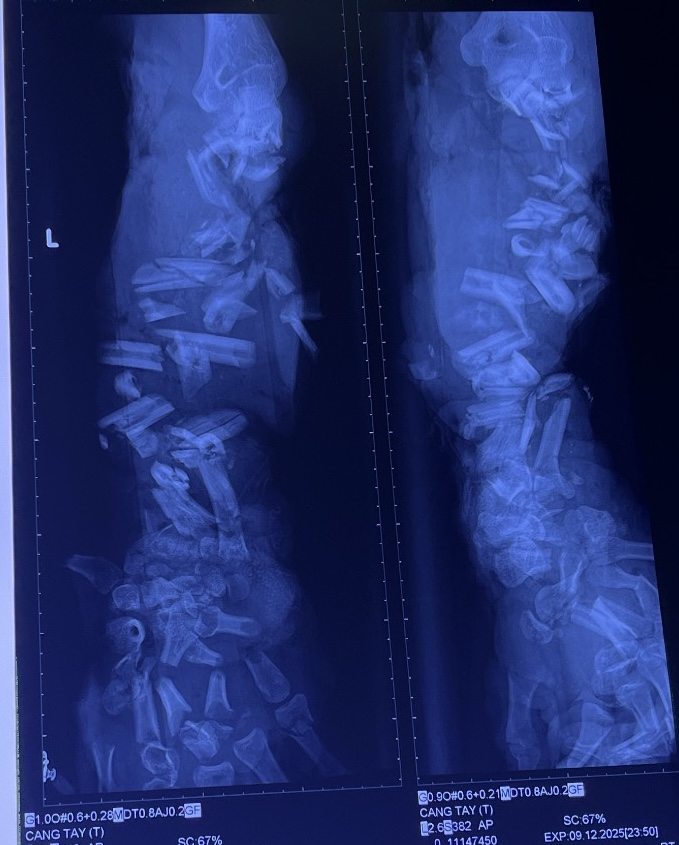

Bệnh nhân đến cấp cứu với tình trạng vết thương dập nát phức tạp rất nặng cánh tay trái (từ cẳng tay đến bàn tay) do máy nghiền vỏ dừa. Xương tay nát đứt nhiều khúc, mô mềm dập nát nặng, tím tái, dính nhiều đất cát và dầu nhớt.

Hình ảnh phim X – quang cho thấy xương cẳng tay và bàn tay trái của bệnh nhân bị gãy từng khúc, không còn hình dạng của xương quay và xương trụ